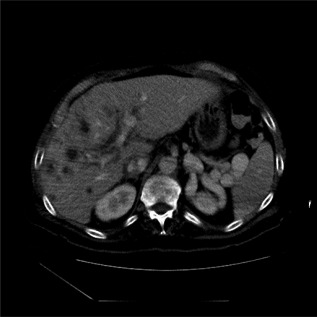

Figure 3.

Ischemic biliary injury with multiple fluid collections in liver (right lobe and perihilar) in a patient with ischemic cholangiopathy (recipient of a donation after cardiac death allograft).

Biliary strictures develop in 5% to 15% of deceased donor liver transplant recipients and up to 28% to 32% of living donor liver transplant recipients.10 They are classified as either anastomotic strictures (ASs) (Fig. 1) or nonanastomotic strictures (NASs) (Fig. 2) and differ in terms of pathophysiology, clinical course, and response to therapeutic interventions. ASs tend to be single, short in length, and localized to the anastomosis site, whereas NAS are more likely to be multiple, longer, and are often intrahepatic or in the donor duct proximal to the anastomosis.10 NASs are especially important because early biliary complications tend to present before ASs (mean 3.3‐5.9 months) and are more likely to result in graft loss.5, 10 Similarly, ischemic cholangiopathy is characterized by diffuse intrahepatic strictures and bile leaks/collections (bilomas) (Fig. 3) in the absence of HAT/stenosis and may result in worse outcomes. Incidence of ischemic cholangiopathy is reported at 2% to 20% in some series and is particularly important in the setting of donation after circulatory death grafts with a significantly higher incidence in this population compared with donation after brain death grafts.11